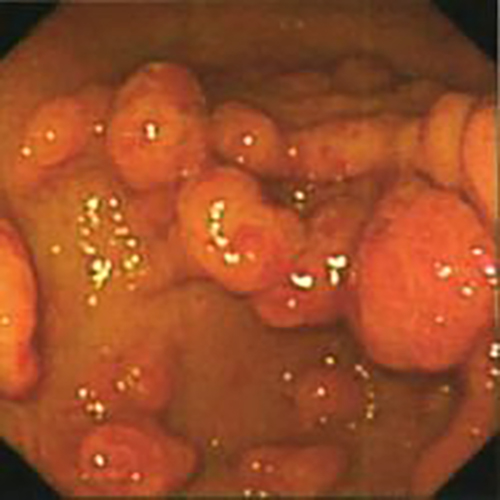

增生性胃息肉

增生性胃息肉常見症狀

增生型胃息肉

早期良性胃息肉